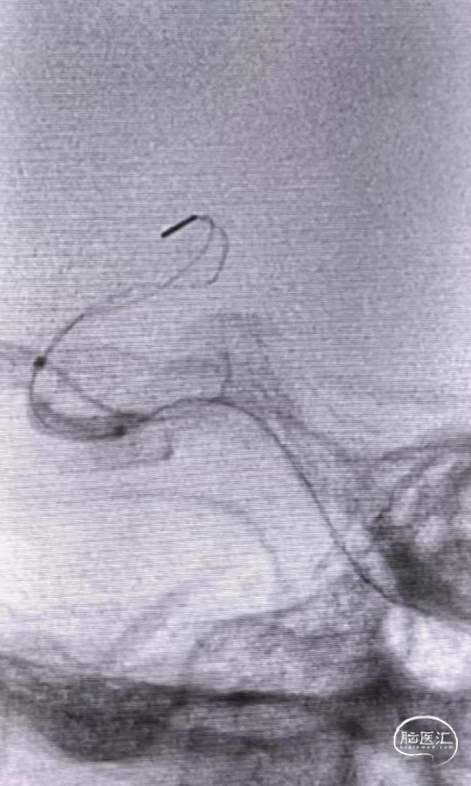

依次从远心端到近心端释放4.5*37mm EP支架、4.5*30mm EZ支架、7*40mm 自膨式支架覆盖夹层明显处后造影示:右侧颈内动脉畅通,远端血流mTICI 3级。

术后即刻影像及患者术后情况:术后患者即可恢复清醒,无神经系统缺损体征,术后24小时复查头颅CT示: